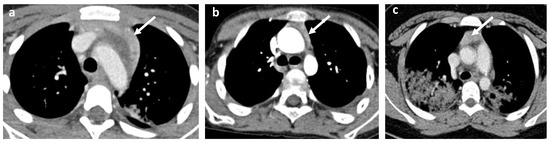

- Cervical, mediastinal, and axillary lymphadenopathy.

- Cardiovascular abnormalities including cardiomegaly (Figure 1c) and signs of pericarditis, myocarditis, and pericardial effusion.